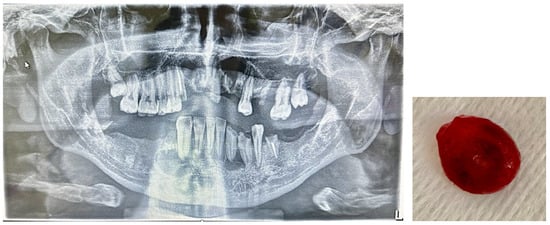

2.1. Study Design and Participants

2.2. Inclusion Criteria